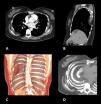

Axial (A) and sagittal (B) CT with contrast, with reconstructions (C,D), in which a convex lens-shaped herniation and incarceration of soft tissue of the right posterior wall of the thorax (subcutaneous fat layer and major rhomboid muscle) can be observed in the pleural cavity via the widened space between the sixth and eighth ribs.

A 45-year-old woman was admitted with a 10-day history of chest pain in the posterior part of the right side, with no other associated symptoms. Ten years earlier, she had undergone resection of the seventh rib due to a costal hemangioma. A MDCT was performed, which revealed the presence of a convex lens-shaped herniation and incarceration of soft tissue of the right posterior chest wall (subcutaneous fat layer and major rhomboid muscle) in the pleural cavity through a widened intercostal space between the sixth and eighth ribs (Fig. 1). The thoracic surgeon responsible for the treatment opted to perform an exploratory thoracotomy via this interspace, but no masses were observed in the chest wall during the procedure. The thoracotomy incision was closed carefully with strong stitches to prevent recurrence of the hernia. Post-operative recovery was uneventful and the patient was discharged with no symptoms.